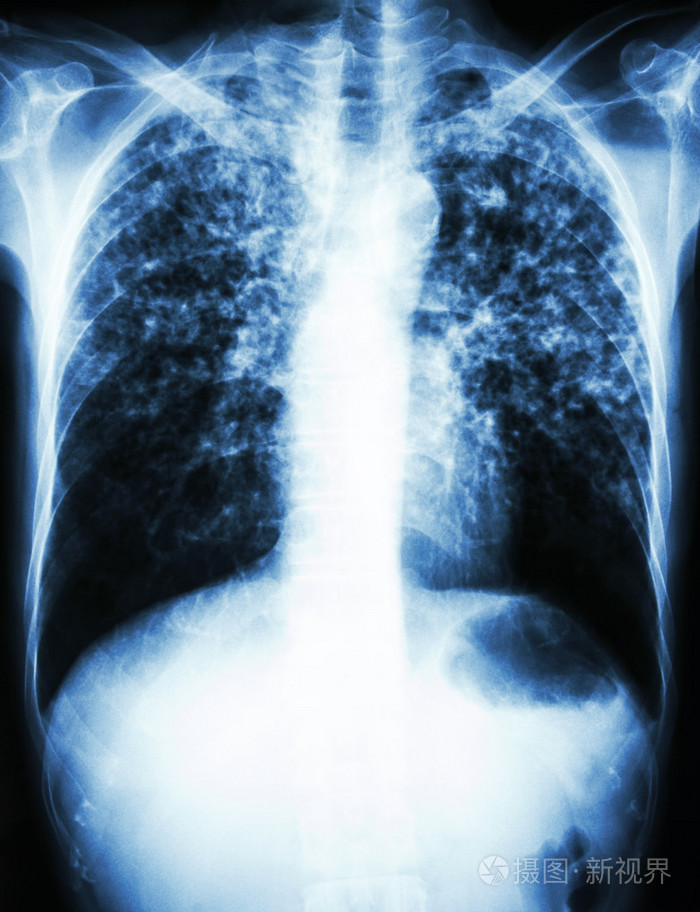

胸部x光显示晚期肺结核

肺结核. 旧病人的胸部x线片